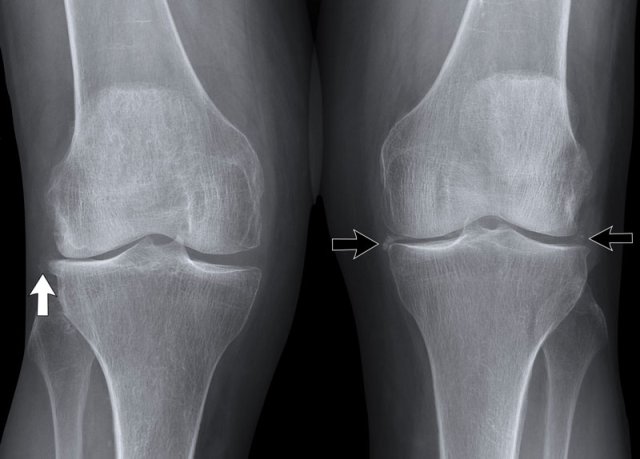

Click on image to enlarge. Click on image to enlarge.

1. Typical osteoarthritis with cartilage loss on the medial side, subchondral sclerosis and osteophytes.

2. There is uniform cartilage loss.

There are no osteophytes.

In such a case your first thought should be inflammatory joint disease.